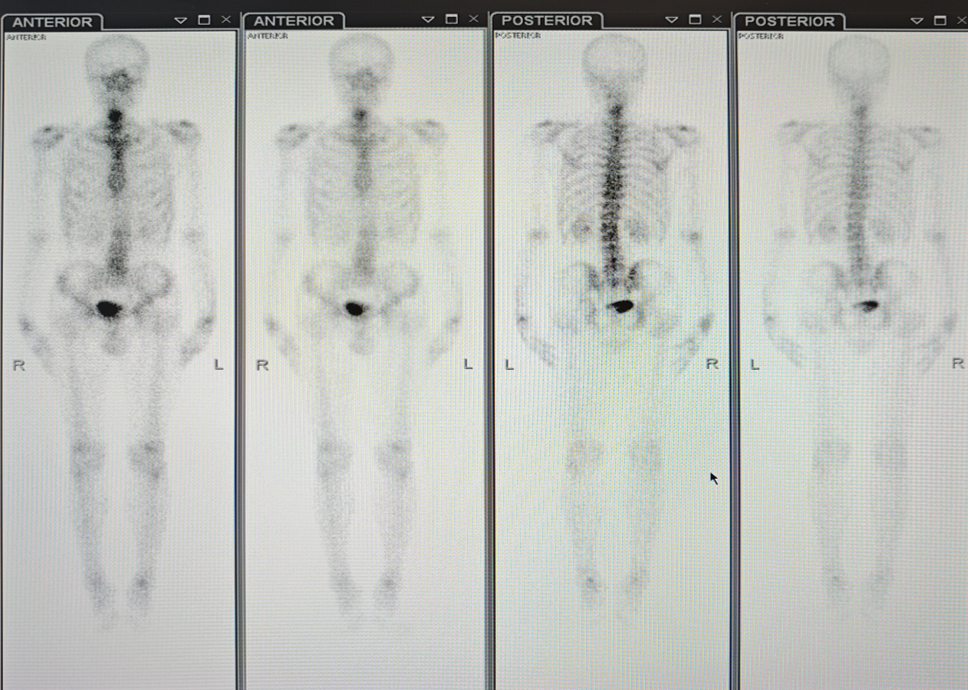

ECT:全身骨骼显影清晰,颈椎下段(具体节段不详),第4、9、10胸椎,第1、2、4、5腰椎,左侧踝关节见异常放射性核素分布浓聚,余处骨未见异常放射性核素分布浓聚和稀疏。膀胱过度充盈,部分盆腔骨骼显影不清。

颈椎增强MRI: 颈椎序列不稳,曲度过弯;颈椎退变。部分椎体异常信号,随诊复查。C4-7间盘膨出。

MDT 意见:科室开展 MDT 讨论,影像科排除骨转移,认为肺部结节暂无法定性,建议定期复查,综合团队意见采用新辅助治疗后再行手术的策略。